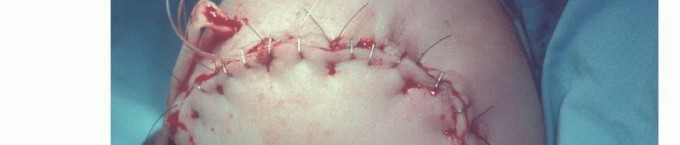

- يتم عمل شقوق في الجلد والعضلات بشكل يسمح بتكوين طيات جلدية (Skin Flaps) كافية لتغطية نهاية العظم المقطوع بشكل جيد ودون شد، مما يقلل من خطر مشاكل الجروح.

- تُخاط طيات الجلد فوق العظم والعضلات المشكلة بعناية فائقة.

- يتم تطبيق ضماد معقم.